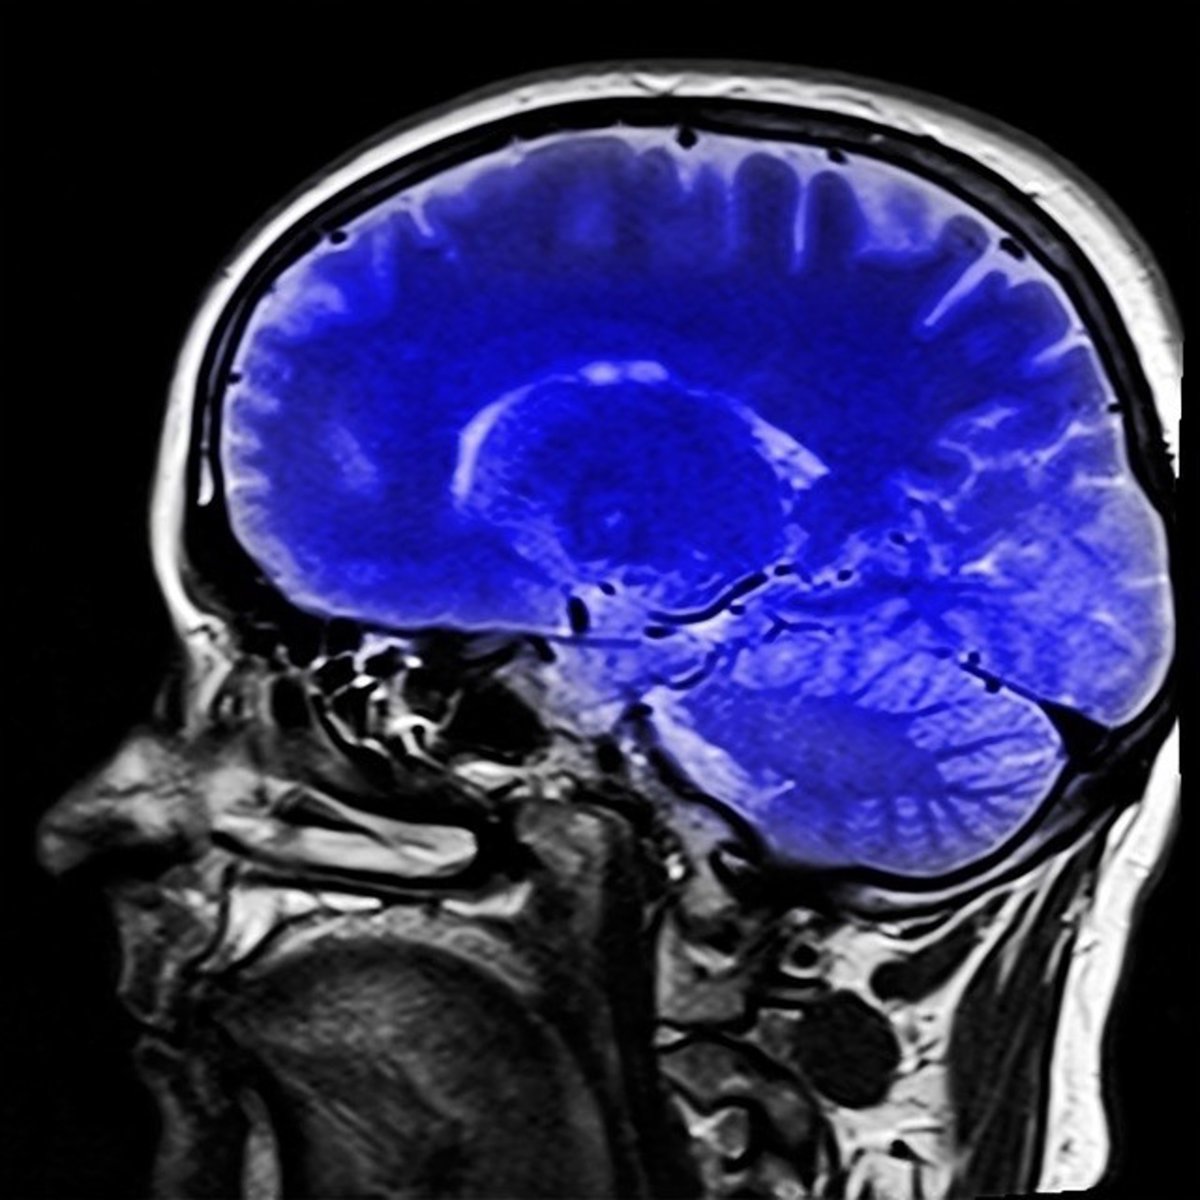

Resonancia magnética del cerebro

PIXABAY